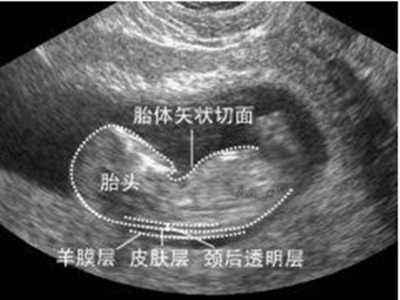

2)孕期11~14周

第二次的B超检查 , 有其特别之处 , 就是要进行“唐氏筛查” 。 如若胎儿颈顶透明层NT>3cm , 那么染色体可能发生异常 。

文章图片

孕妈妈一定要配合 , 不然会影响NT值的准确测量 。 NT需要结合宝宝的位置测量 , 孕妈妈要耐心的等待 , 必要时还需进行第二次的测量 。